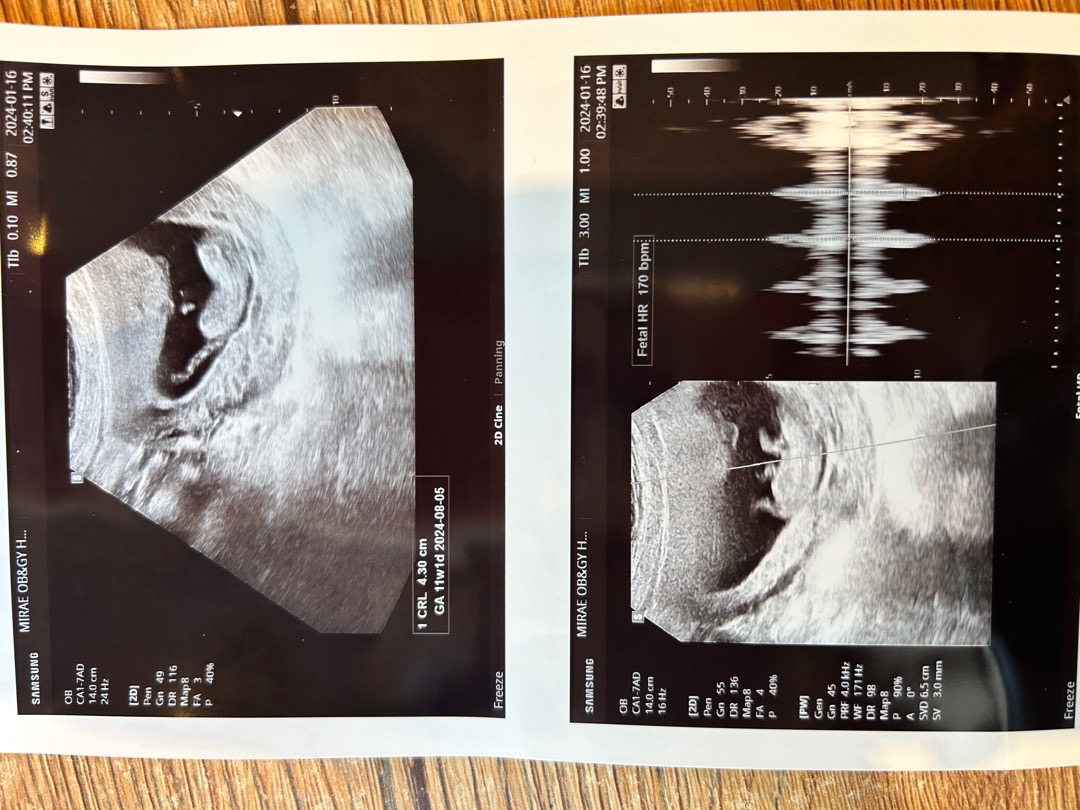

초음파 젤리곰 대신 개구리

다른분들 초음파사진 보면 젤리곰 하리보 그러셔서 저도 기대했는데 오늘 10주 4일째 초음파봤는데 개구리 뒷다리 봤네요 심장소리도 일정하지 않고 중간에 이상하게 들려서 놀랐는데 아기가 계속 노는중이라 제대로 안잡혀서 그런거라고 잘크고 있다고 안심하래요 다리가 길다니 좋은 소식이지만 이런 초음파도 있답니다..🤣 다들 놀라시는거 같아서 사진 수정해서 올려요 둘다 오늘 찍힌 사진인데 다리 모양이 다르죵

아니,, 저기 제눈에보이는게 다리 맞죠? ㅋㅋㅋ 10주차에 저렇게 긴 다리가 있다니! 태어나면 모델준비하셔야겠네요 ㅎㅎㅎ 신기하네요🥰🥰 건강하다고 하니 다행입니다~^^

우와ㅡ 다리길이 무엇이죠🤩🤩🤩🤩 10주차중에 제일 롱다리인것같아요!!!!!!!!!

오잉??탯줄아니에용????다리면 진짜 기네요 !